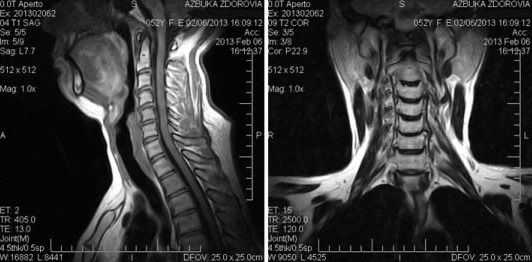

Магнитно-резонансное сканирование: шейный отдел позвоночника в сагиттальной плоскости на Т1 ВИ

В назначенное время пациент пребывает в клинику. После заполнения добровольного медицинского согласия, беседы для выявления возможных противопоказаний и сдачи на хранение всех предметов, содержащих металл, рентгенлаборант провожает испытуемого в диагностическую комнату и укладывает на стол томографа. Для нивелирования технического шума можно воспользоваться берушами или наушниками. Удобство и максимальную неподвижность обеспечивает фиксация конечностей мягкими ремнями.

Наблюдение за ходом диагностической процедуры медперсонал осуществляют через стекло из смежной комнаты, общение происходит по громкой связи. Для получения более качественных томограмм на область шеи накладывают катушку-усилитель.

Каких-либо болевых ощущений во время обследования нет. По команде медтехника стол с пациентом скользит внутрь кольца барабана. Иногда требуется на несколько секунд задержать дыхание. Под воздействием магнитного поля и радиоимпульсов ионы водорода в составе молекул воды изменяют привычное положение, при возвращении на место происходит выброс энергии, фиксируемый датчиками. Полученную информацию анализирует компьютерная программа и скульптурирует многоплоскостные изображения с нужной толщиной среза.

Как выглядит снимок МРТ шейного отдела?

МРТ шейного отдела позвоночного столба: сколиоз (коронарная плоскость, Т2 ВИ)

При описании хода диагностической процедуры врач-рентгенолог обращает внимание на соответствие полученных изображений всех внутренних структур шеи принятым нормам. Для обывателя снимок МРТ позвоночника выглядит как серо-бело-черная абстракция. При более внимательном рассмотрении на сканах различимы контуры головы, позвоночный столб, спинной мозг и пр. Самостоятельно расшифровать магнитно-резонансную томограмму и обнаружить некоторые патологии невозможно, даже специалисты с опытом работы периодически пользуются специальными атласами.

Для качества сканов важны характеристики томографа: оптимально пройти исследование на аппарате (лучше экспертного класса) с закрытым контуром и мощностью от 1,5 Тесла. Сканеры со слабым магнитным полем (от 0,15 Тл) выдают малоинформативные данные, особенно, если необходима оценка мелких деталей.